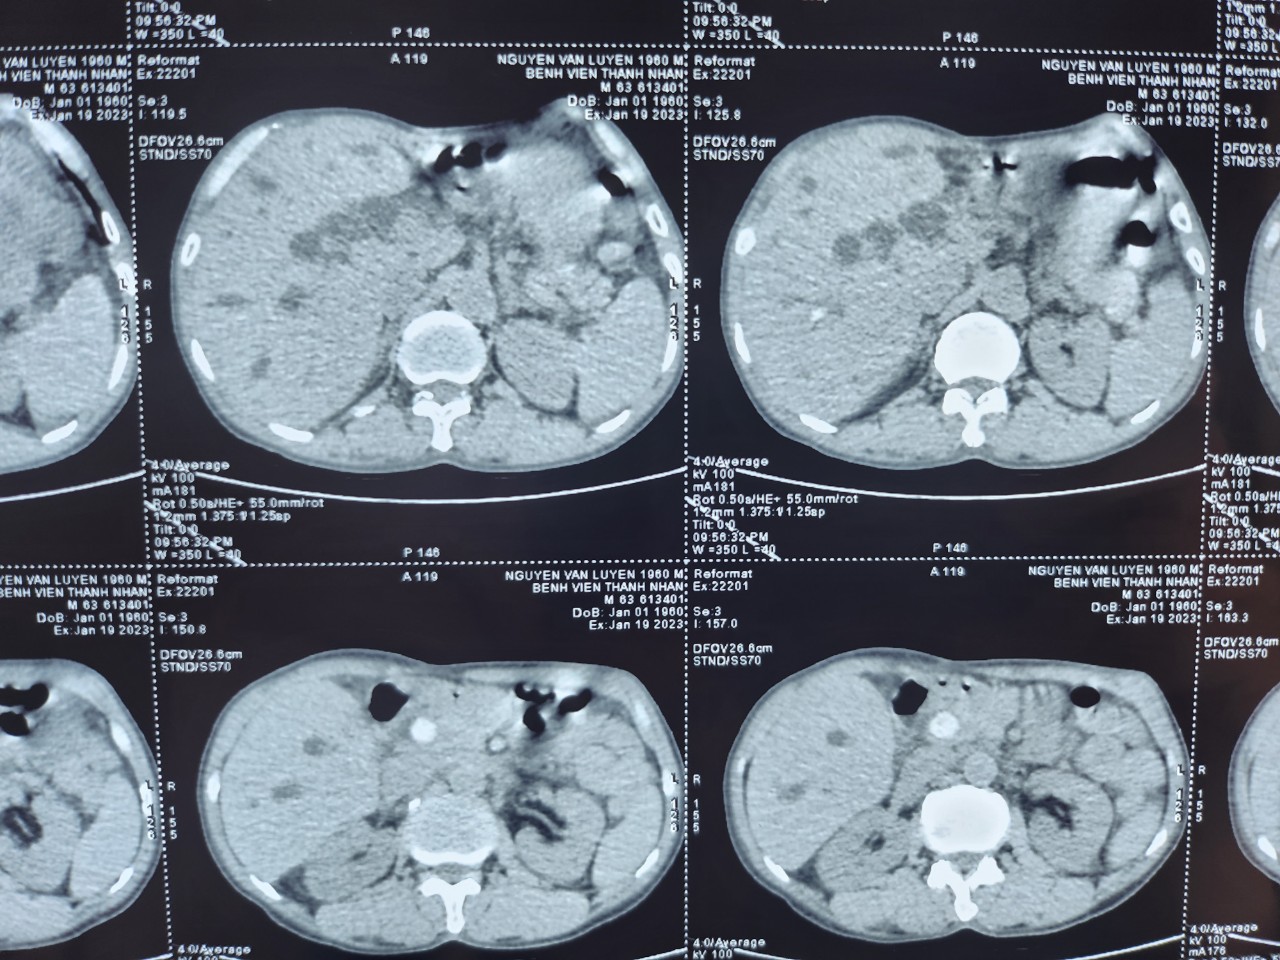

Tháng 1 năm 2023, khoa Ngoại tổng hợp 1 bệnh viện Thanh Nhàn tiếp nhận bệnh nhân nam 63 tuổi vào viện vì sốt cao và đau bụng, bệnh nhân có tiền sử mổ sỏi mật 2 lần. Bệnh nhân được làm bilan chẩn đoán: Tắc mật do sỏi ống mật chủ tái phát

Hình 1: Phim chụp trước mổ